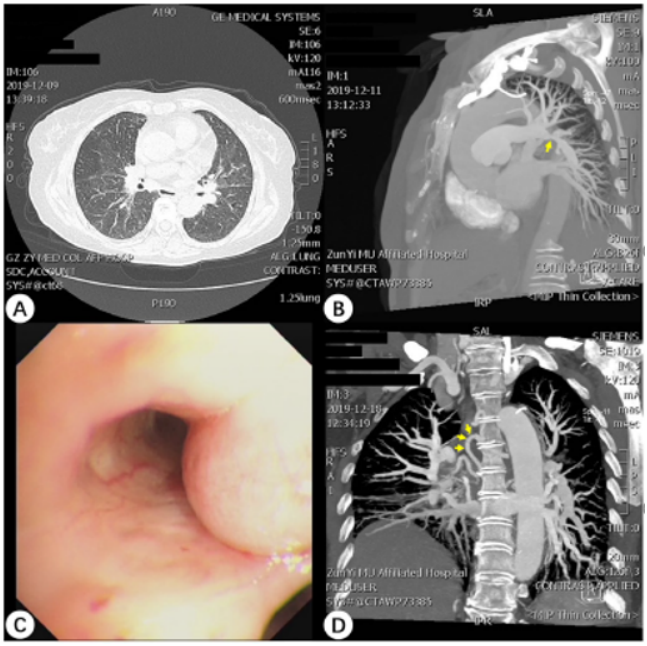

患者10余天前出现咯血,于当地医院接受了抗感染、止血等治疗,治疗后咯血好转。胸部CT(2021-05-14,外院):两肺炎症,散在纤维条索影(图1)。5月17日气管镜提示左肺下舌段管口可见肉芽增生,活检后明显出血(图2)【活检组织并未送病理】,量约500 ml,SpO2降至65%。立即予止血、吸氧等治疗,咯血量减少。但患者仍反复咯血,5月17日转入ICU,予有创机械通气、止血治疗。

图1  患者外院胸部CT(2021-05-14)

图片

图2  患者支气管镜检查(2021-05-17)